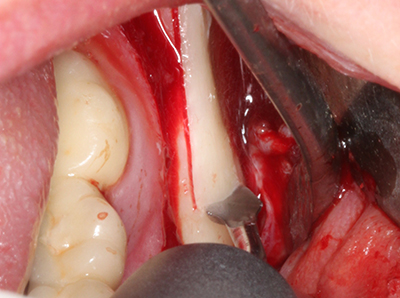

Sollen chirurgische Eingriffe mit unmittelbarer Knochenbeziehung an empfindlichen Strukturen wie Blutgefäßen oder Nerven erfolgen, so bergen rotierende Instrumente ein erhebliches Potential an iatrogener Schädigung. Gerade bei Nervdarstellungen nach iatrogener Schädigung, oder aber im Zuge einer Nervlateralisation für resektive und rekonstruktive Eingriffe oder Implantatinsertionen können piezoelektronische Geräte hilfreich sein Knochendeckel zu präparieren und nervnahe Hartgewebsanteile zu entfernen (Abb. 17-20). Ein leichter Kontakt des Nervstrangs zur Piezospitze bleibt dabei in der Regel folgenlos – allerdings kann eine unvorsichtige Vorgehensweise mit sägeartigen Bewegungen bzw. Ansätzen bei noch vorhandener knöcherner Unterlage durchaus temporäre oder aber auch permanente Nervschädigungen verursachen. Das Risiko einer solchen Schädigung wird jedoch als wesentliche geringer eingeschätzt als unter Anwendung von Säge- oder Fräsinstrumenten (Pereira, Gealh et al. 2014).